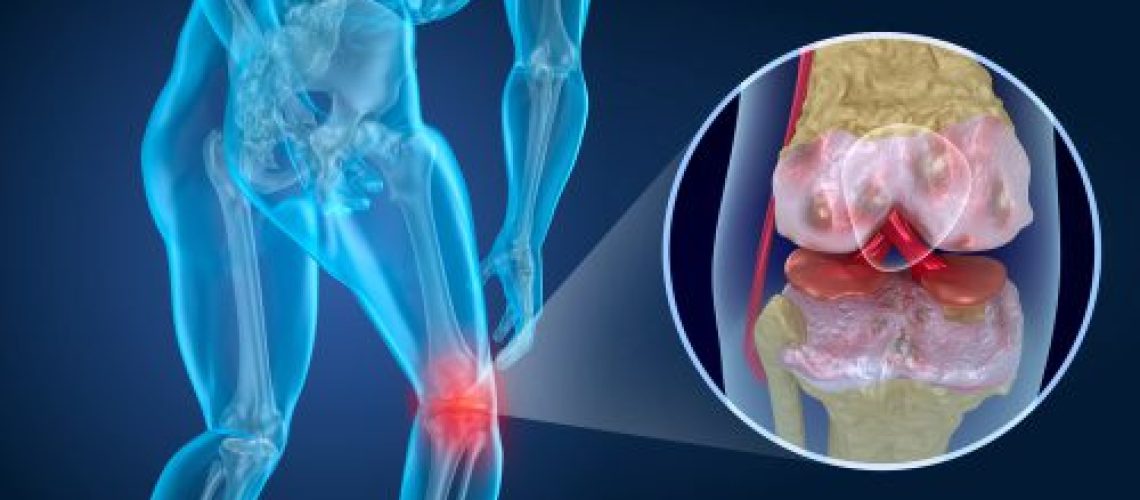

A artrose nos joelhos é uma doença que desgasta a cartilagem que reveste as extremidades ósseas, provocando processos inflamatórios e a degeneração das articulações. A artrose é mais comum em pessoas com mais de 65 anos e do sexo feminino, uma vez que esses perfis possuem uma estrutura óssea mais frágil.

O primeiro sintoma, e mais recorrente, é a dor. Ela tende a acentuar-se ao fazer movimentos, como subir e descer escadas, sentar-se ou praticar exercícios físicos que exijam impacto. Além da dor, surge o inchaço no joelho. Ele é provocado por uma inflamação na membrana sinovial, que recobre a articulação do membro.

Quando a membrana se incha, ela pode acentuar ainda mais as dores, uma vez que há mais pressão na área. A perda progressiva do movimento e a incapacitação ocorrem em casos de artrose, por isso, o problema deve ser tratado para evitar tal estágio.